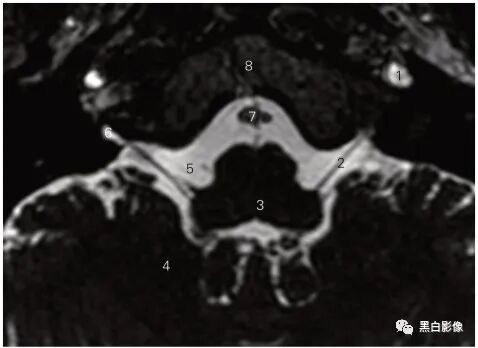

图5-2 经视神经的冠状断层MR T2加权图像

1 眼动脉 ophthalmic artery 2 外直肌 lateral rectus

3 视神经鞘 sheath of the optic nerve

4 筛骨鸡冠 crista galli of ethmoid bone

5 下直肌 inferior rectus 6 内直肌 medial rectus

7 蛛网膜下隙 subarachnoid space 8 视神经 optic nerve

9 眼上静脉 superior ophthalmic vein